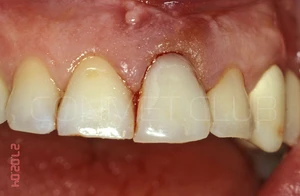

Операция немедленной имплантации была произведена 27.02.2004 года непосредственно после экстракции зуба 21 из-за невозможности дальнейшего лечения данного зуба (две вертикальные трещины корня).

Вид на корень и трещины за три дня до экстракции и немедленной имплантации.